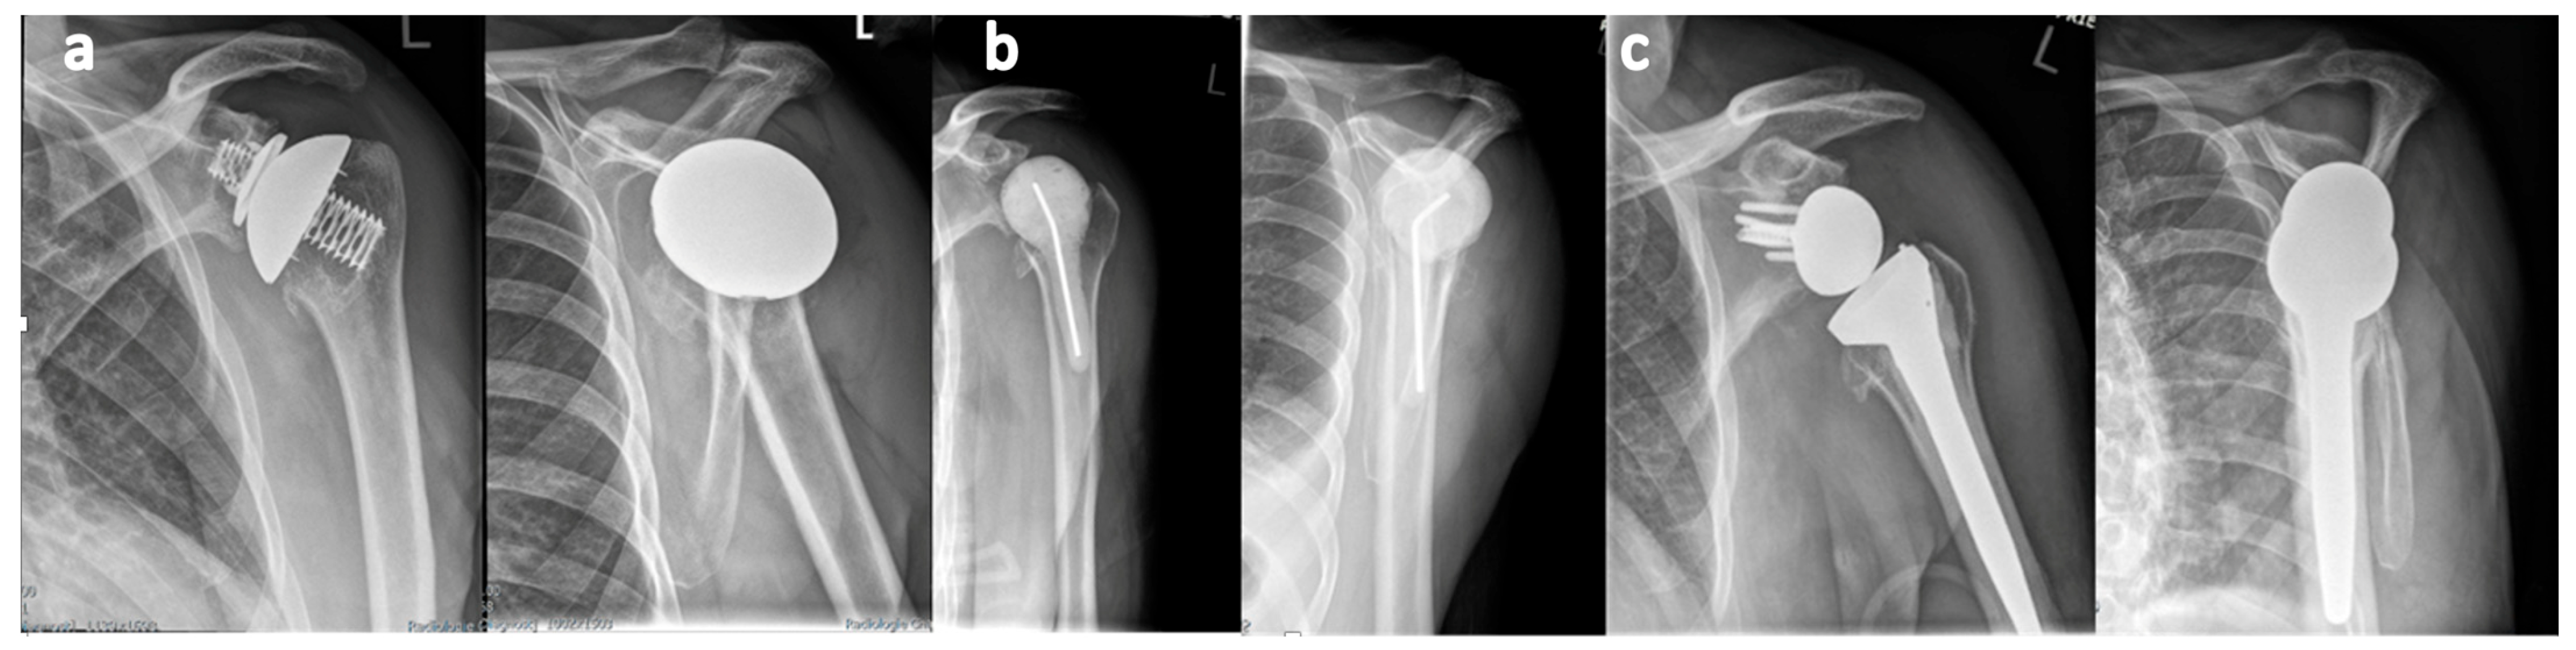

2.3. Two-Stage Revision Arthroplasty Protocol

3.1. First Stage

3.2. Second Stage